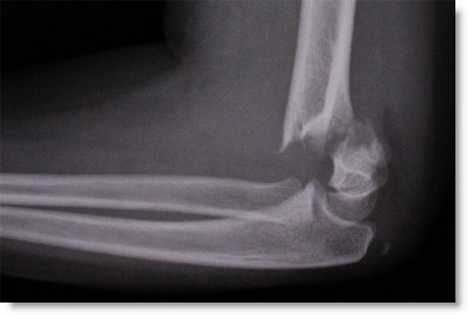

Elbow Fractures & Breaks

Elbow fractures can occur following falls or direct impact to the elbow. It is extremely important for an early accurate diagnosis. This can usually be obtained with an x-ray, but in some cases a CT scan may be required. It is important to rehabilitate the elbow correctly to prevent any pain or stiffness in the long-term. If you do have a suspected elbow fracture, it is important to contact the team at shoulder, elbow, hand early, so that x-rays can be reviewed prior to your consultation.